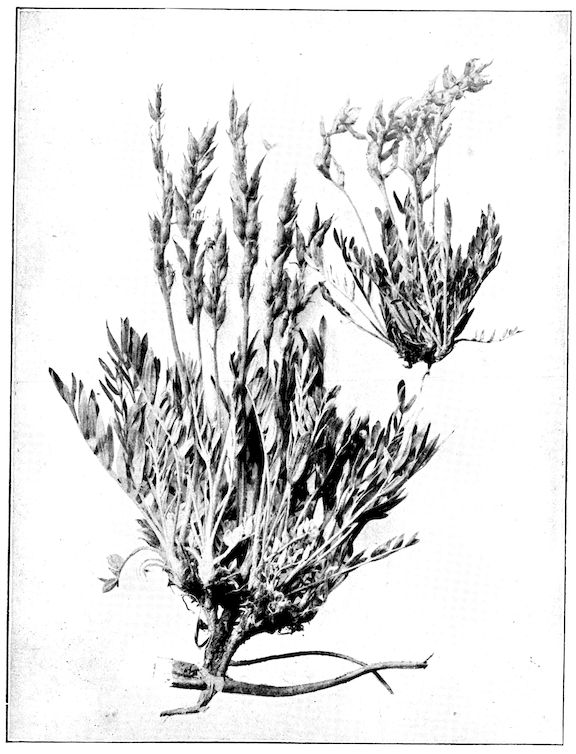

Fig. 3.—Pig suffering from osseous cachexia (fourth stage).

114. The fourth phase, or period of osteomalacia, i.e. softening of the bones, is also the last. It is rarely seen in large animals like horses and oxen, because accidents so often accompany the preceding stages and necessitate slaughter; but it is common in goats and pigs.

Fig. 5.—Head of a pig suffering from osseous cachexia.

Fig. 6.—Osseous cachexia. This condition developed in two months, the last month of gestation and the first of lactation.

Fig. 7.—Osseous cachexia: softening of the maxillæ.